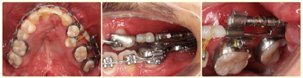

2.外科辅助放置牙支持式牵张器(图5):上颌弓丝换至0.019*0.025"SS",外科于左侧24、26根尖下0.5mm处做梯形切口,行骨皮质切开术,粘接牙支持式骨牵张器;牵张器由螺旋扩弓器(杭州新亚,0.4 mm螺距)制成,打磨抛光多余金属部件,焊接于24、26带环;术后7 d开始加力,每日1次,每次旋转1/2圈,2周复诊1次。

3.开辟足够间隙,稳定后开始唇向牵引25(图6)。

牙支持式牵张成骨术[4],即将牵张器固定在牙上,经水平根尖下及牙根间垂直截骨形成牙骨复合体,以连续的牙列作支抗,通过螺杆的旋转牵张力将牙骨复合体送到预定的位置,在牵引力作用下促进新骨的生成,实现骨缺损的修复。常作用于存在大量牙槽骨组织缺损导致植骨难以存活,需要在缺损区形成连续的牙槽骨桥的唇腭裂患者[4,5];也可以用于牙槽裂间隙小,无法通过常规牙槽骨移植修复的患者[6];同时,在缺损的上下颌骨中需要获得充足牙槽骨量及软组织覆盖的病例中,也可选择使用[7]。该方法优点在于保留牙齿,解除拥挤,增加骨量,避免广泛的牙槽骨移植,促进腭咽功能[4];牵张同时产生了新的牙槽骨和牙龈,用于快速正畸牙齿移动[4,8]。有学者[9,10]认为该术式损伤小,有效牵张时间短,患者接受度好,简单高效。由于传统牵张中采用的截骨术创伤大,易发生分离骨段骨坏死,故本病例仅在根尖下行部分骨皮质切开,以期刺激牙周骨质反应。牵张后在短时间内分离出足够间隙(近9 mm),稳定1个月后利用滑动杆的刚性,弹性牵引25。最终通过正颌手术解决患者凹面型,术后建立稳定咬合,治疗效果良好,患者满意度高。X片显示牵张段新骨骨量充足,21、23间裂隙减小,牵张过程中患者无明显不适,未出现牙根吸收、松动,周围牙槽骨段连续(图14)。邻牙牙髓活力测试良好,裂隙周围黏膜可见进一步粘连。最终通过正颌手术解决患者凹面型,术后建立稳定咬合,治疗效果良好,患者满意度高。但由于患者治疗中口腔卫生不佳,导致牙颈部出现明显釉质脱矿,需要多学科的进一步治疗。